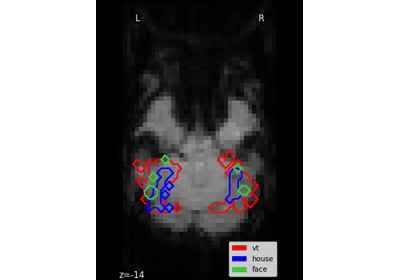

Plot Haxby masks